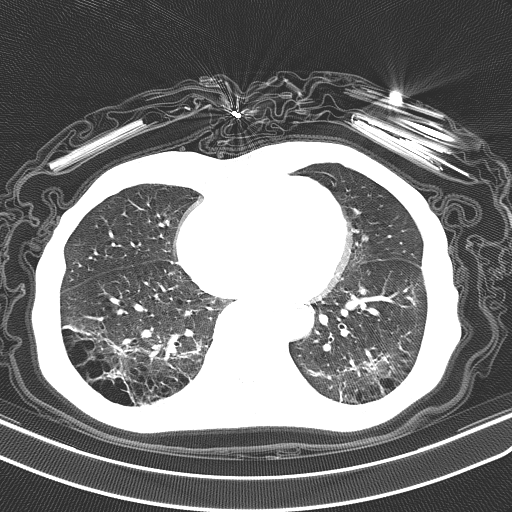

Figure 2: Example chest CT images from the COVIDx-CT dataset, illustrating (a) COVID-19 pneumonia cases, (b) non-COVID-19 pneumonia cases, and (c) normal control cases.

To build the proposed COVIDNet-CT, we constructed a dataset of 104,009 chest CT images across 1,489 patient cases, which we refer to as COVIDx-CT. To generate the COVIDx-CT dataset, we leverage the CT imaging data collected by the CNCB [17], which is comprised of chest CT examinations from different hospital cohorts across China as part of the China Consortium of Chest CT Image Investigation (CC-CCII). More specifically, the CT imaging data consists of chest CT volumes across three different infection types: novel coronavirus pneumonia due to SARS-CoV-2 viral infection (NCP), common pneumonia (CP), and normal controls. Figure 2 shows example CT images for each of the infection types from the constructed COVIDx-CT dataset. For NCP and CP CT volumes, slices marked as containing lung abnormalities were leveraged. Additionally, we excluded CT volumes where the background had been removed to leave segmented lung regions, as the contrast between the background and segmented lung regions can lead to model biases. Finally, we split the COVIDx-CT dataset into training, validation, and test sets, using an approximate 60%-20%-20% split for training, validation, and test, respectively. These sets were constructed such that each patient belongs to a single set. Figure 3 shows the distribution of patient cases and images in the COVIDx-CT dataset amongst the different infection types and dataset splits.